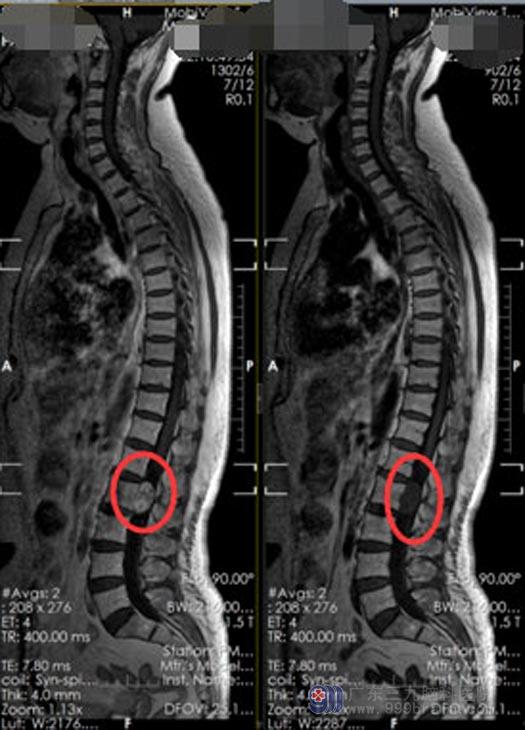

家属多方求医,辗转半年左右时间,他们想起曾经有医生大力称赞过广东三九脑科医院神经外五科,觉得不妨去试试。入院后电生理检查示:1.双侧正常听性脑干反应,2.双侧异常视诱发电位,3.双侧正常上肢深感觉传导通路,4.双侧异常下肢深感觉传导通路。结合全脊柱拼接平扫+增强检查回报:腰2椎水平椎管内左侧占位性病变,考虑神经源性肿瘤,神经鞘瘤可能性大;专科查体:指鼻试验,误指试验阴性,Romberg征睁眼正常,闭目不稳,直线行走试验不稳。

此次手术的重点和难点都在于:充分暴露硬脊膜,小心保护好马尾神经及神经根,严密缝合硬膜,防止脑脊液漏。积极地术前准备后,外五科医生团队在全麻下为陈阿姨实施“经腰2左侧半椎体入路行腰2椎水平椎管内偏左侧神经鞘瘤切除术+硬脑膜修补+腰2半椎体固定术”,术中冰冻考虑神经鞘瘤,肿瘤侵犯硬脊膜,缝合硬脊膜后无脑脊液漏,肿瘤全切,神经保护良好,固定腰2椎椎体后,手术顺利结束。

术后第一天复查腰部CT未见明显出血;术后三天复查腰椎MR显示:原占位性病变全切;病理结果示:椎管内神经鞘瘤。陈阿姨神志清楚,生命体征平稳,无头晕头痛等不适,对答流利,四肢肌力V级,感觉、肌张力正常。肿瘤全切,未出现任何后遗症,家人非常满意此次手术效果。

▲手术前